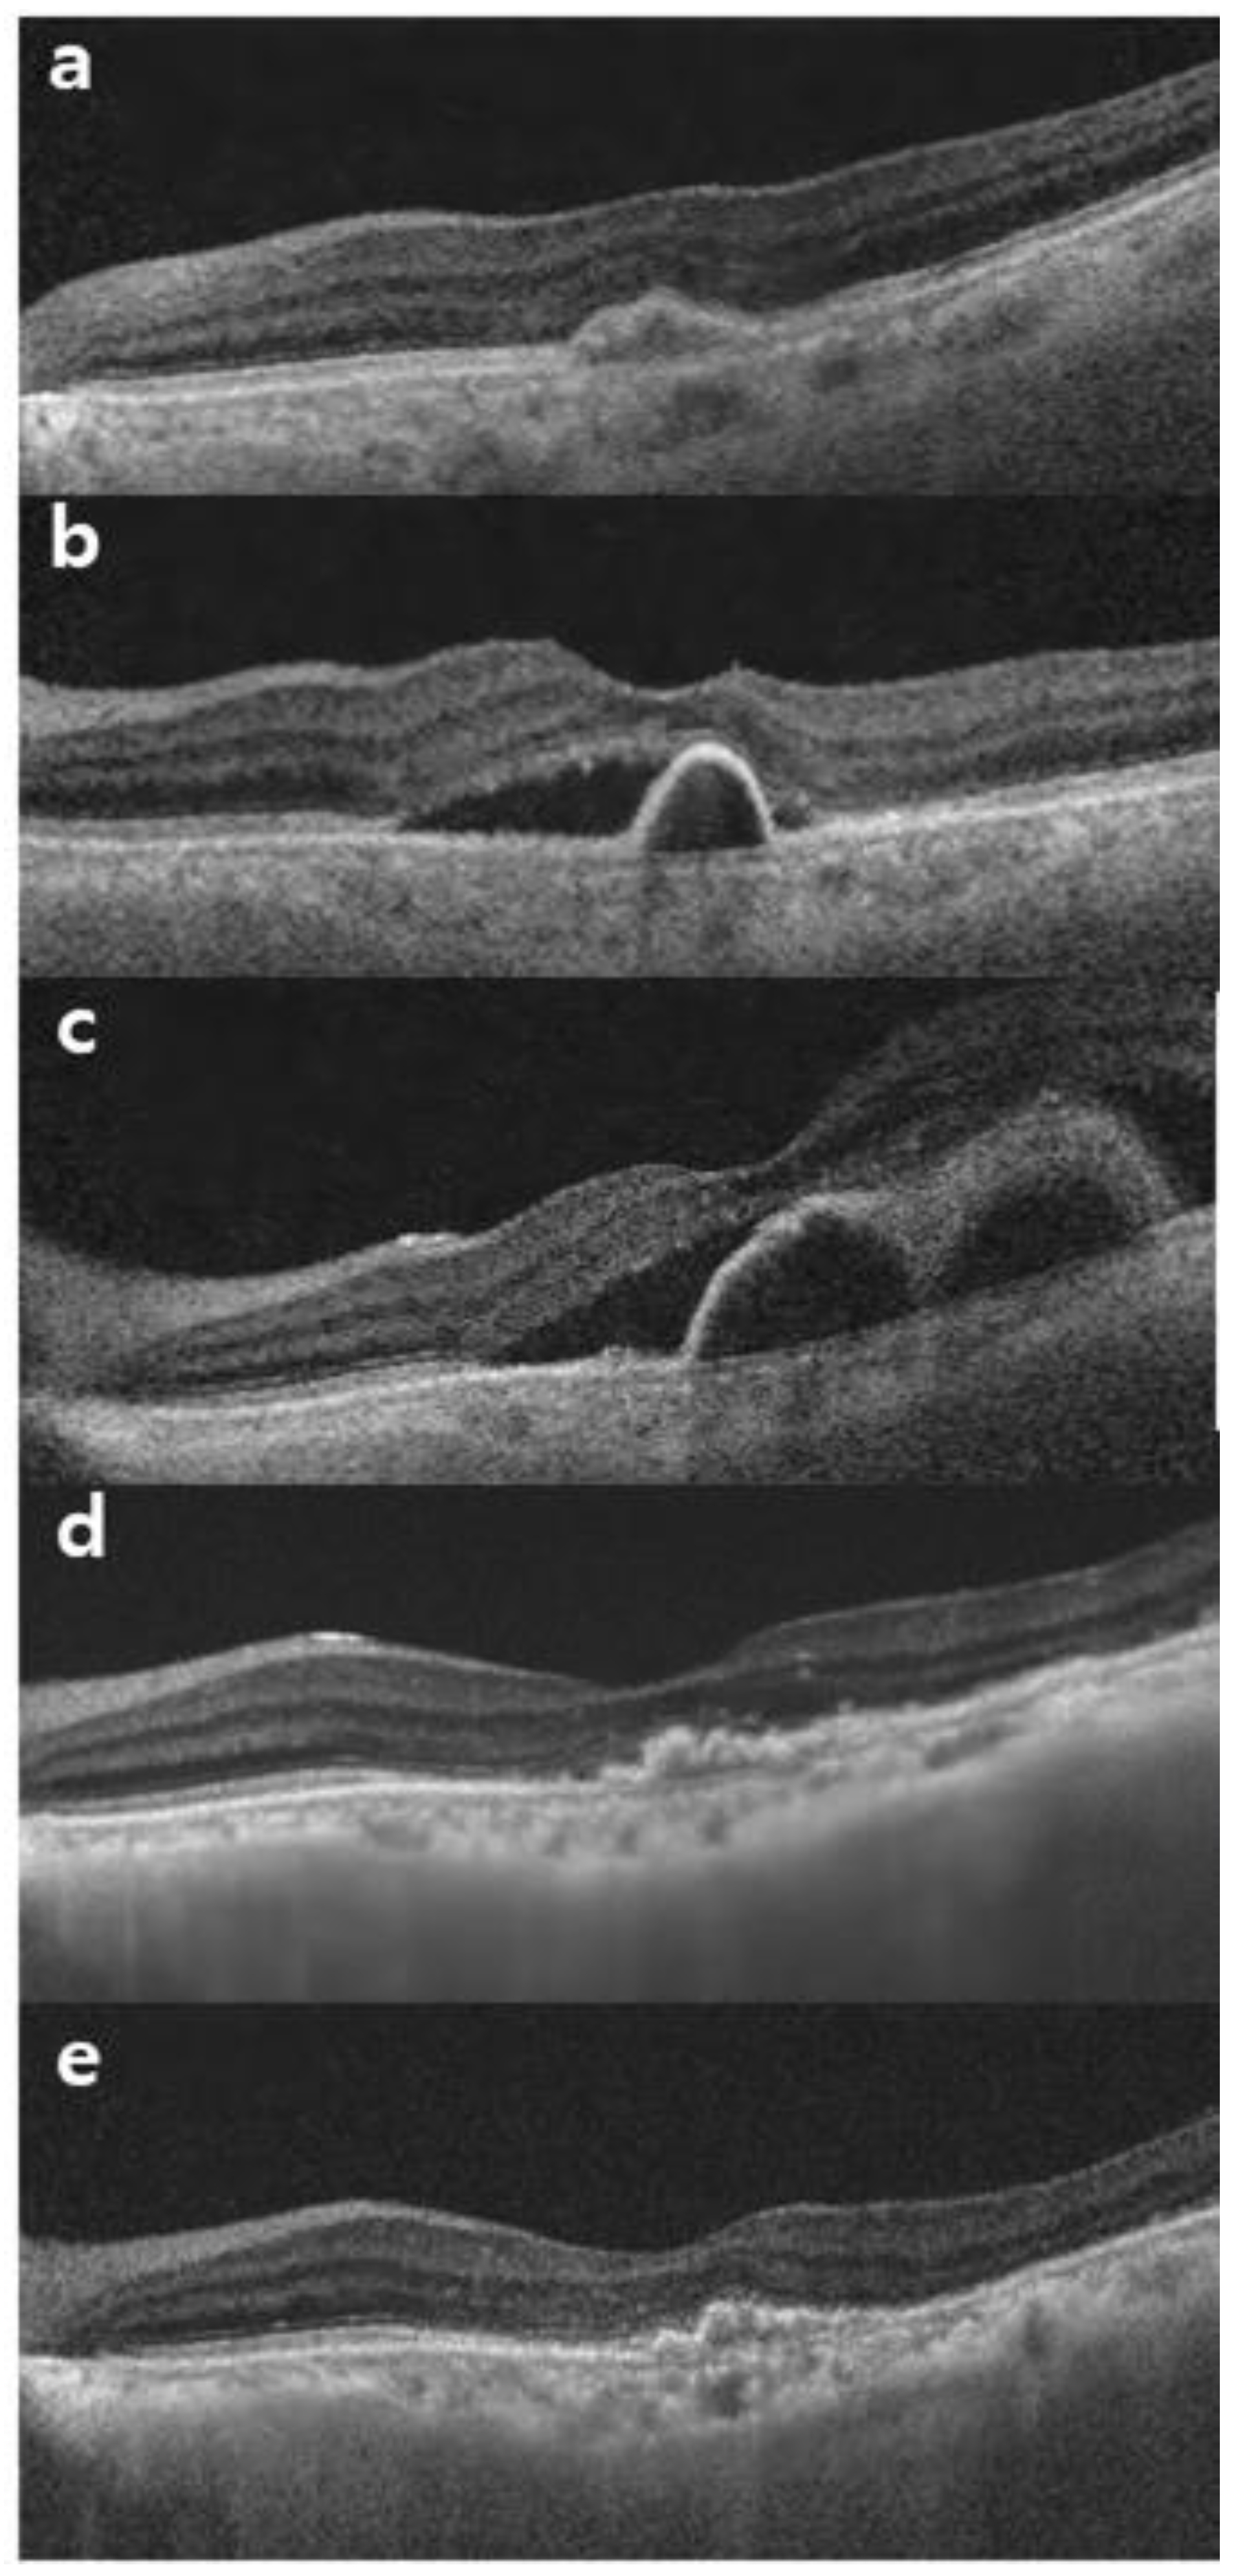

3.3.1. Central Macular Thickness

3.3.2. Pigment Epithelial Detachment Height

3.3.3. Subfoveal Choroidal Thickness

3.3.4. Intraocular Inflammation